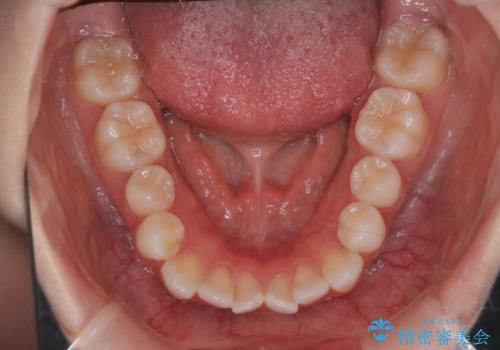

【審美装置】前歯で噛めない!抜歯しないで治したい

- 前歯の捻転とかみ合わせを主訴に来院されました。今回は抜歯をせずにIPRを実施し、並べる計画を立てました。

ワイヤー矯正を行いながら、顎間ゴムを患者さまにご協力していただき、短い期間で終了できました。